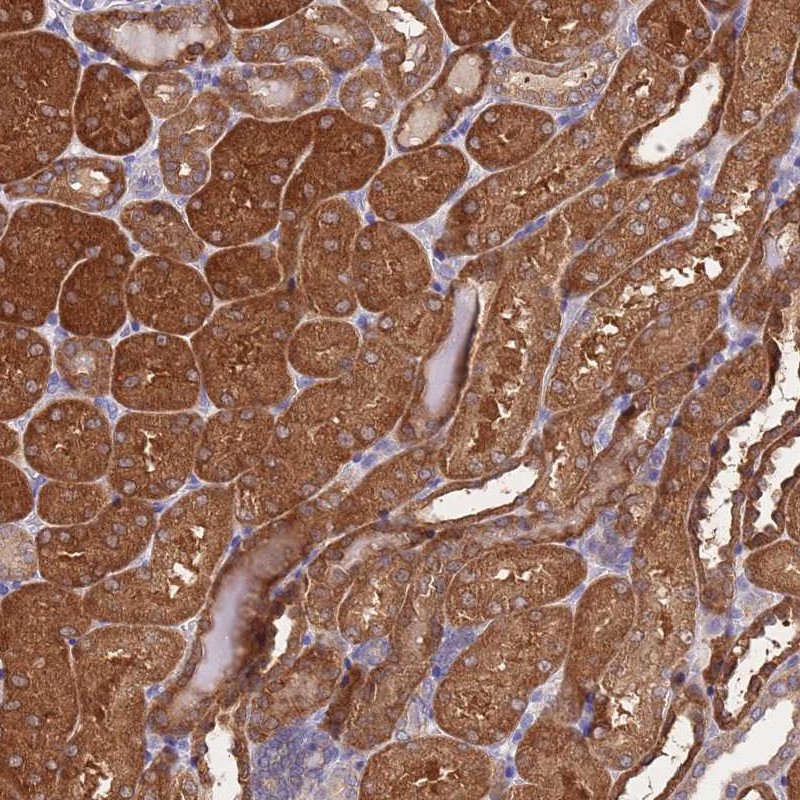

Immunohistochemical staining of human kidney shows strong cytoplasmic positivity in renal tubules.